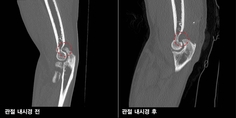

뼈와 뼈가 연결되는 부위인 관절에 퇴행성 변화나 외상 등 여러 원인으로 인해 염증이 생긴 것을 관절염이라고 한다. 대부분의 사람들은 관절염의 개념을 무릎으로 국한하는 경우가 많은데, 사실 관절염은 관절 부위 어디든 발생할 수 있는 질환이다. 특히 팔꿈치는 의외로 관절염이 자주 발생되지만, 생소하게 느껴지는 발병 부위로 여겨지고 있다. 서울부민병원 김성준 과장은 “설거지, 걸레질 등 일상적인 가사일에서도 무릎만큼이나 팔꿈치가 많이 사용되며, 직업군에 따라서도 팔꿈치 관절염으로 통증과 불편함으로 내원하는 경우도 상당수”라고 설명했다. 반복적인 팔꿈치 사용, 외상 후 치료 제대로 못 받아도 발생 대부분의 관절염 양상이 그러하듯 팔꿈치 역시 반복적인 관절 사용으로 인해 퇴행성 관절염으로 이어지는 비중이 가장 높은 편이다. 특히 손이나 팔 힘을 반복적으로 사용하거나 물건을 들어올리는 등 어깨 높이에서 팔을 올리고 일하는 직업군에서 팔꿈치 관절염이 발병되는 편이다. 유통업이나 기계 정비업, 목수 등의 직업군에서 발병되는 비율이 높은 편이며, 반복적인 가사일로 인해 주부 역시 팔꿈치 관절염에서 자유로울 수 없다. 뿐만 아니라 팔꿈치 관절을 반복적으로 사용하는 바이올리니스